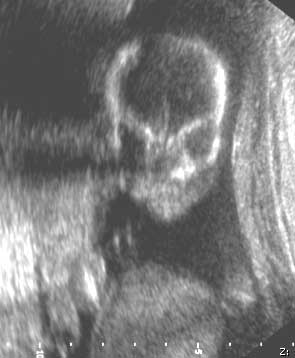

Cara del feto - tercer trimestre del embarazo

Nota: Las imágenes se muestra para fines ilustrativos. No trate de sacar conclusiones comparando esta imagen con otras en el sitio. Solamente los radiólogos calificados deben interpretar las imágenes.